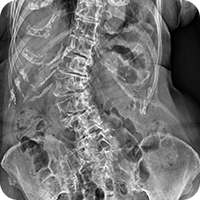

척추는 우리 몸의 중심에 위치하여 기둥의 역할을 수행하는 구조물로,

위쪽으로는 머리를 받치고 아래쪽은 골반과 연결되어 있습니다.

33개의 작은 척추뼈들이 쌓여져 하나의 척추를 이루며,

각 척추뼈 사이에는 디스크가 위치합니다. 그리고 주변에 근육과

인대가 붙어 부족한 안정성을 보완하고 운동성 향상의 기능을 수행합니다.